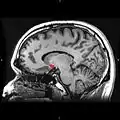

Nucleus accumbens

Approximate location of the nucleus accumbens in the brain